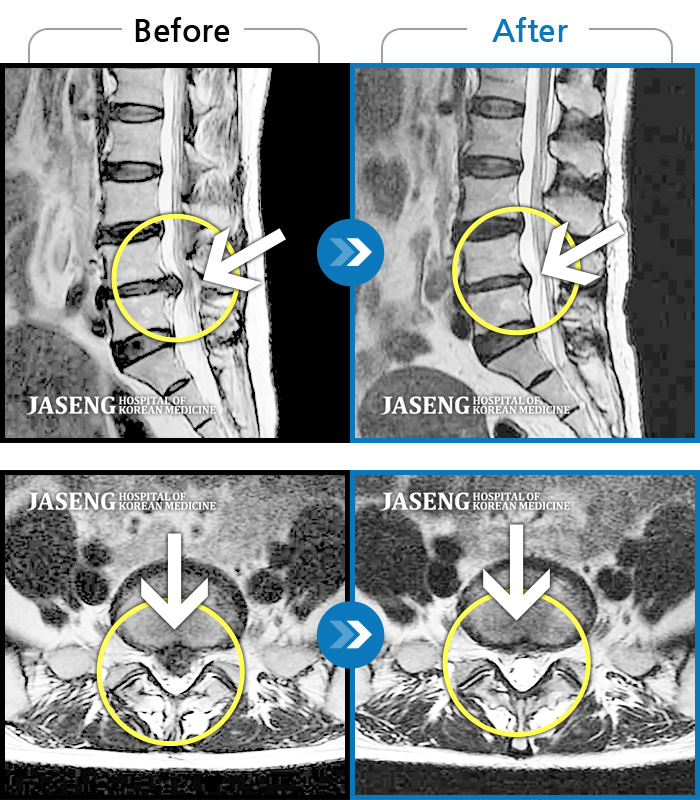

허리디스크

안산 · 김민수 원장

허리가 아프고 두 다리가 저려서 조금만 걸어도 주저 앉아야 했습니다.

촬영시기

2018.12.20 ~ 2023.02.21

2023.02.24